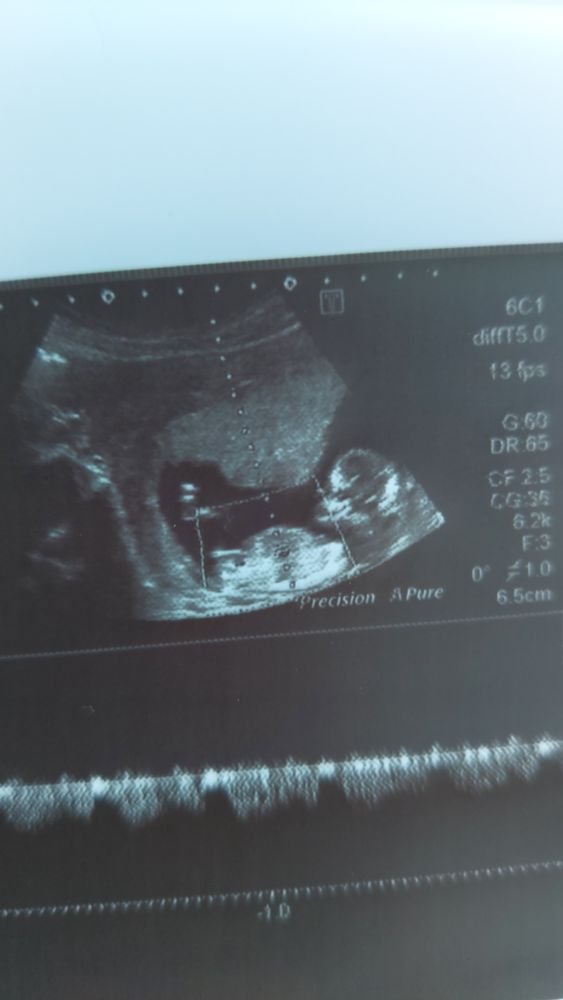

Дочка или сыночек?😏

Yuliia, видите палочка между ножек параллельно спинке? Это половой бугорок девочки) у моей такой же лично на узи видела)

Yuliia, у мальчика чуть под углом

Мама2021, Ваш комментарий явно выделяется😏 но я так и не врубилась че все так однозначны, ножки вижу, а с бугорком не ясно где он точно и действительно ли параллельно спинке🤔